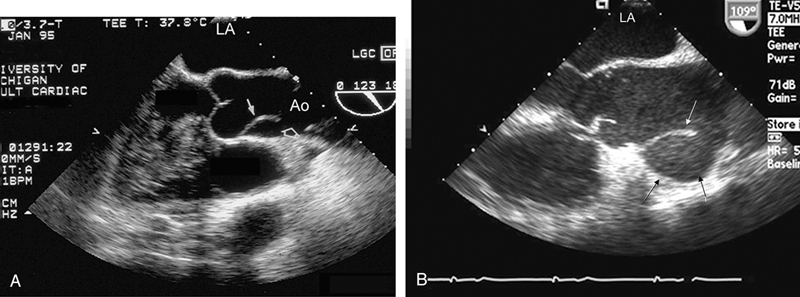

فحوصات تشخيصية لبعض امراض القلب والشرايين التاجية